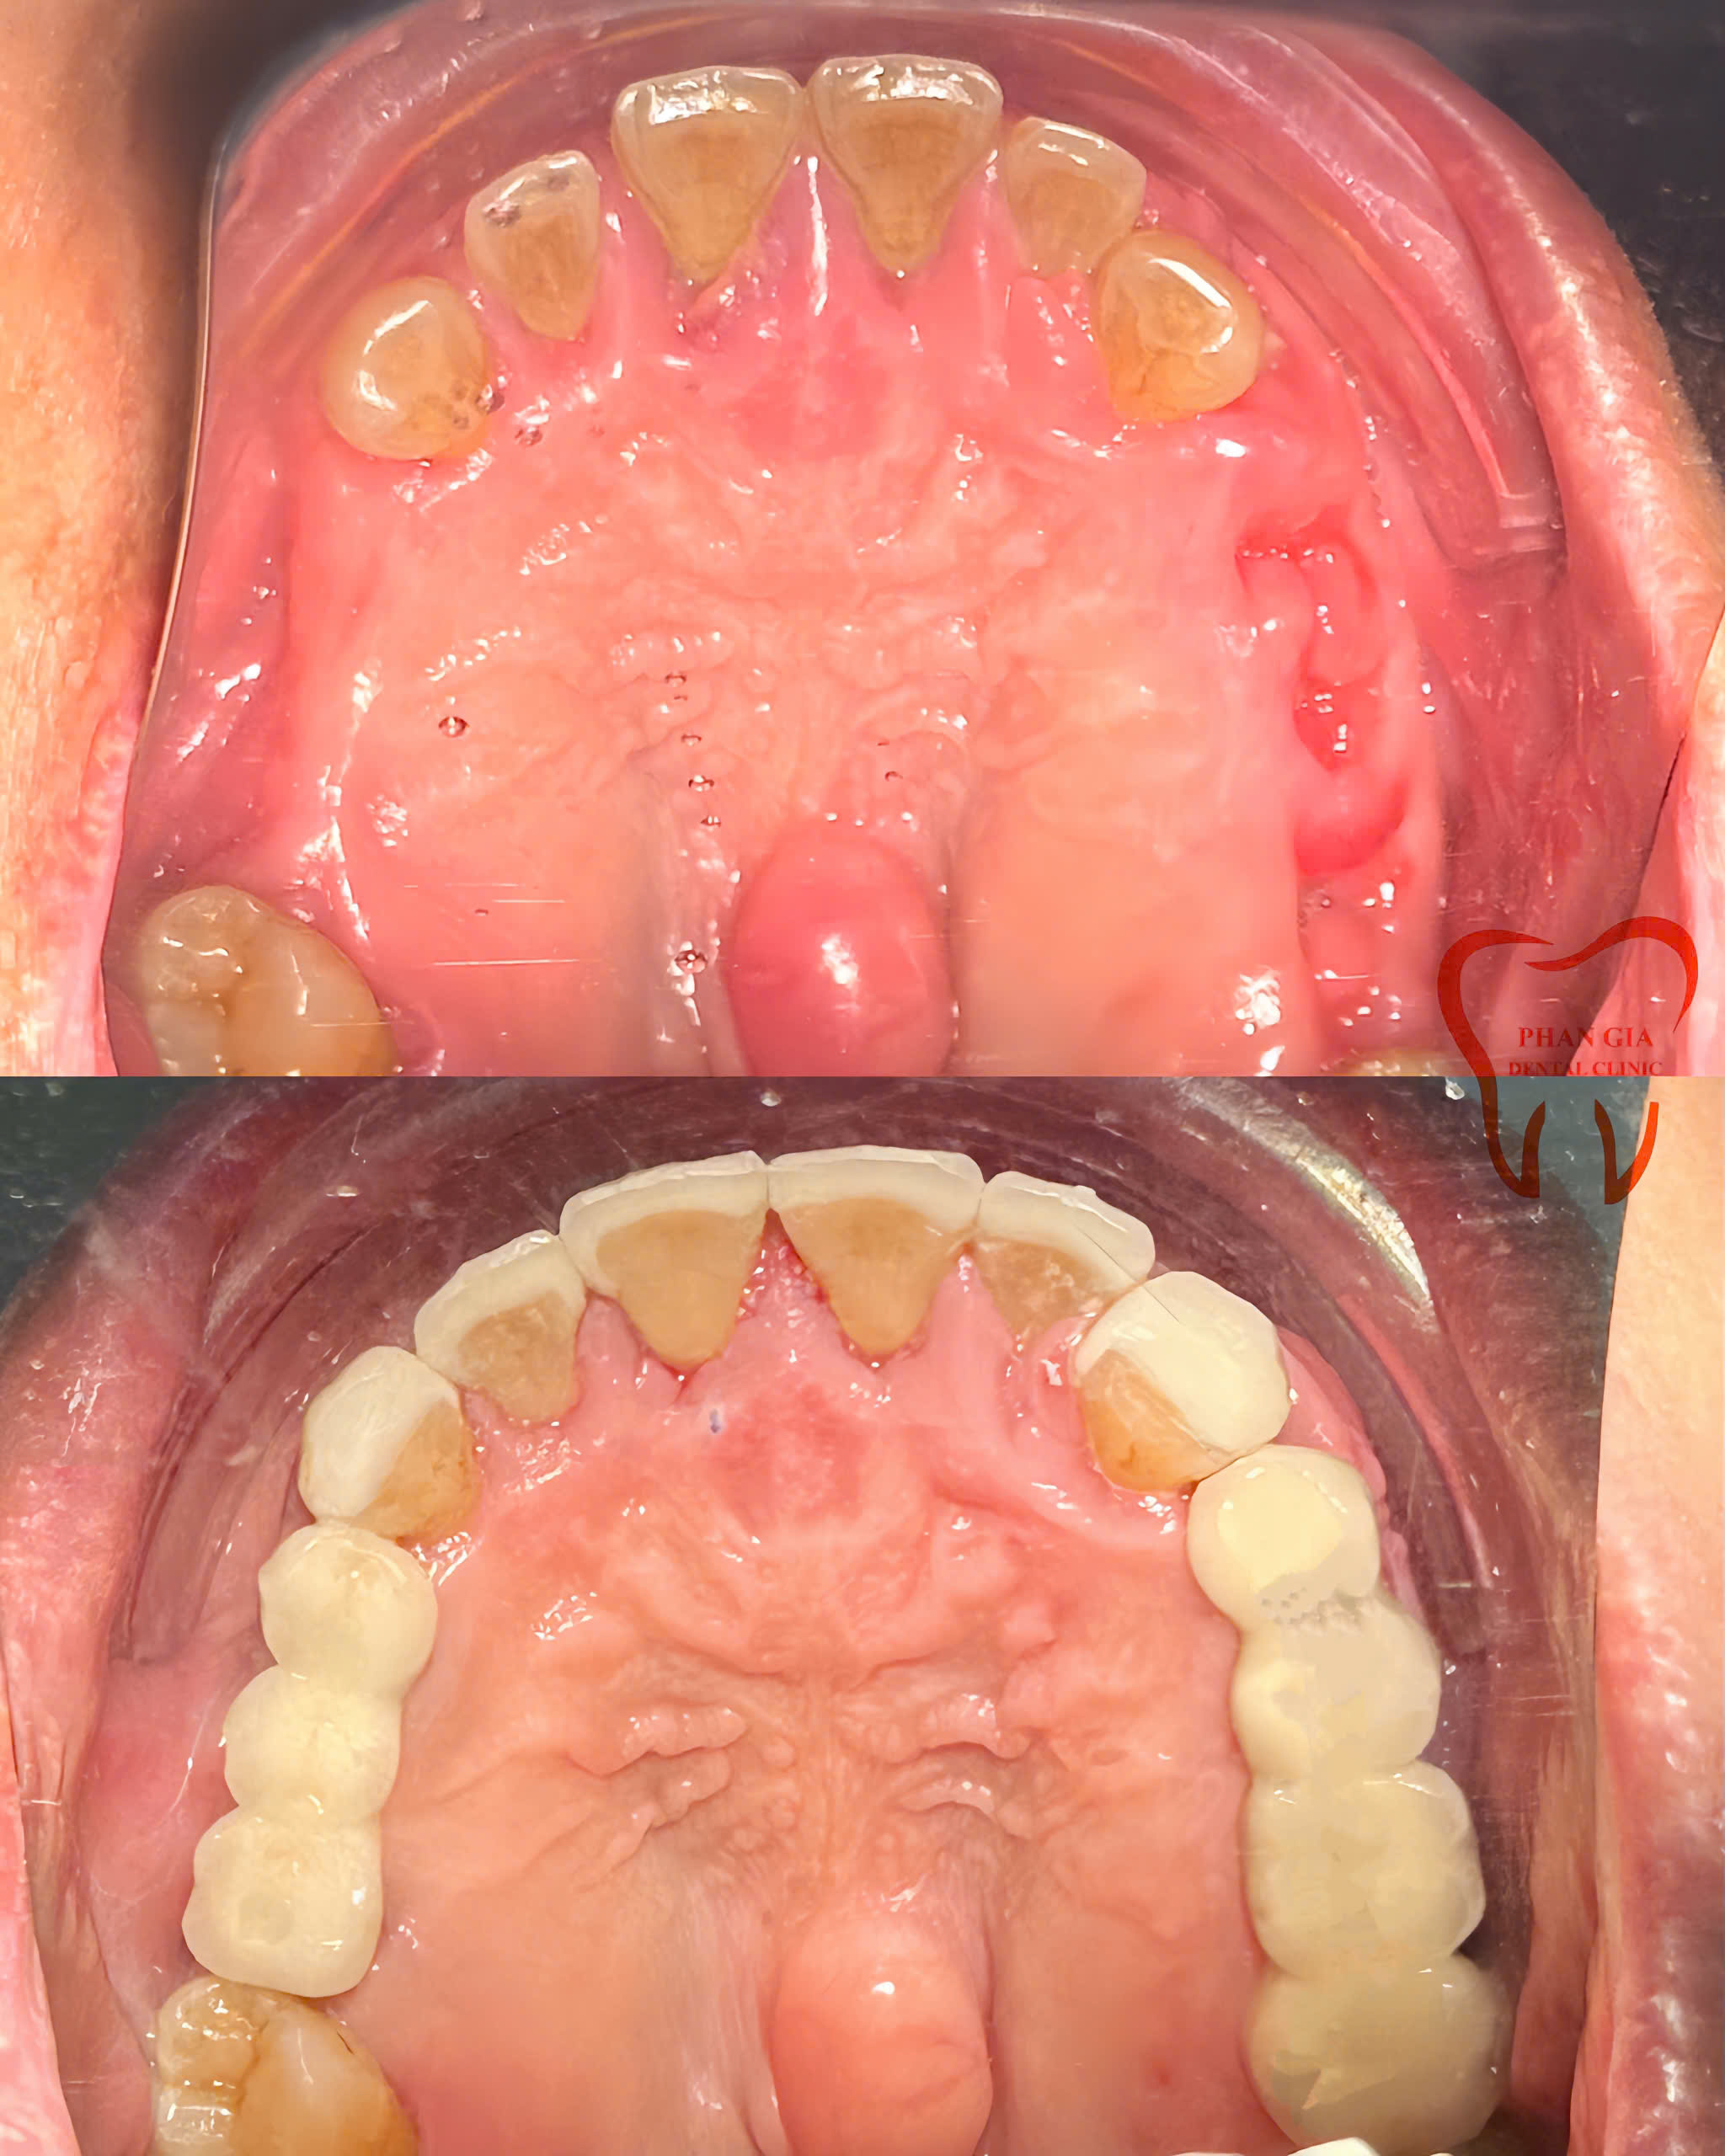

Hình ảnh minh họa hoàn thiện case cấy ghép implant và làm cầu rcầg trên implant

Khách hàng Việt Hồng, trường hợp chị Hồng trước đây bị răng sâu vỡ lớn không thể giữ lại và 1 số R bị viêm nha chu, tụt nướu lộ chân R bắt buột phải nhổ. Bác sĩ tư vấn chị nên trồng lại các răng đã bị mất để có thể ăn nhai thoải mái trở lại do răng hàm trên của chị vẫn còn và chị vẫn còn trẻ.

Đặt hết niềm tin vào trình độ và tay nghề của đội ngũ Bác sĩ tại PHAN GIA chị quyết định lựa chịn cắm mỗi bên phân hàm 2 trụ implant rồi làm răng sứ lên đó để có răng ăn nhai trở lại.

Chú THÙY một trường hợp có kinh nghiệm sử dụng 2 phương pháp phục hình chất lượng nhất hiện nay: Làm cầu răng Full Sứ và cầu răng Sứ Trên Implant. Trước đây chú đã làm cầu 3 răng sứ hàm dưới tại nha khoa PHAN GIA, lâu dài răng hàm trên của chú cũng bắt đầu gặp vấn đề một số vị trí, bác sĩ đã tư vấn cho chú nên cắm implant rồi làm cầu răng sứ trên implant sẽ sử dụngbền và chắc chắn hơn .Tin tưởng các bác sĩ của PHAN GIA chú THÙY lựa chọn cắm implant và làm cầu răng sứ trên implant cho hàm trên của chú.